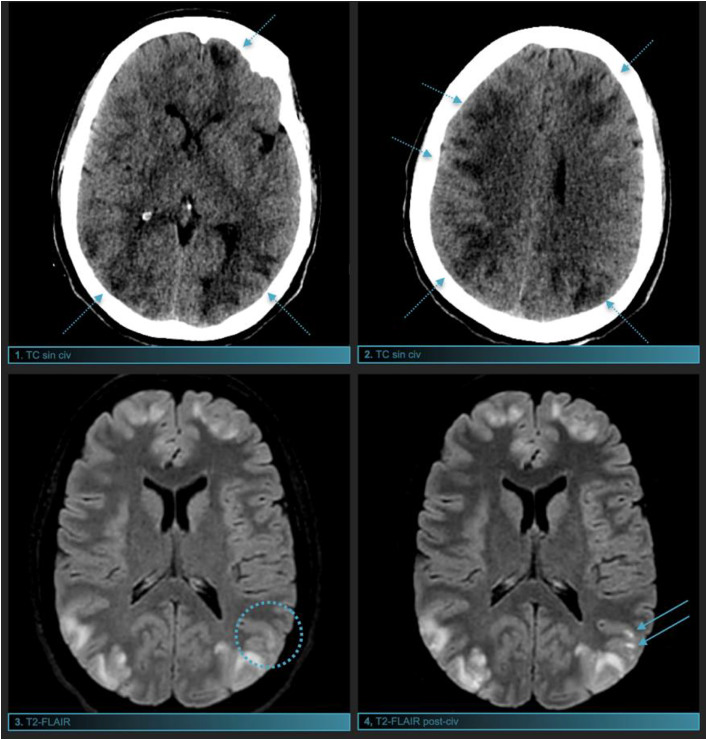

Clinical case: 29-year-old young man who goes to the emergency room with abdominal pain, vomiting and seizures. To determine the underlying cause, a brain computed tomography (CT) and magnetic resonance imaging (MRI) were performed, confirming the presence of involvement at the parieto-occipital level. Laboratory and urine tests are positive for porphyria, with improvement and resolution of the condition through targeted treatment.

Discussion: Porphyrias are rare metabolic disorders with dominant autonomic inheritance that affect heme biosynthesis. In a minority of cases, an external factor can trigger a crisis producing abdominal and neurological symptoms. Imaging findings in acute porphyria are characteristic of PRES (posterior reversible encephalopathy syndrome), with cortico-subcortical involvement.